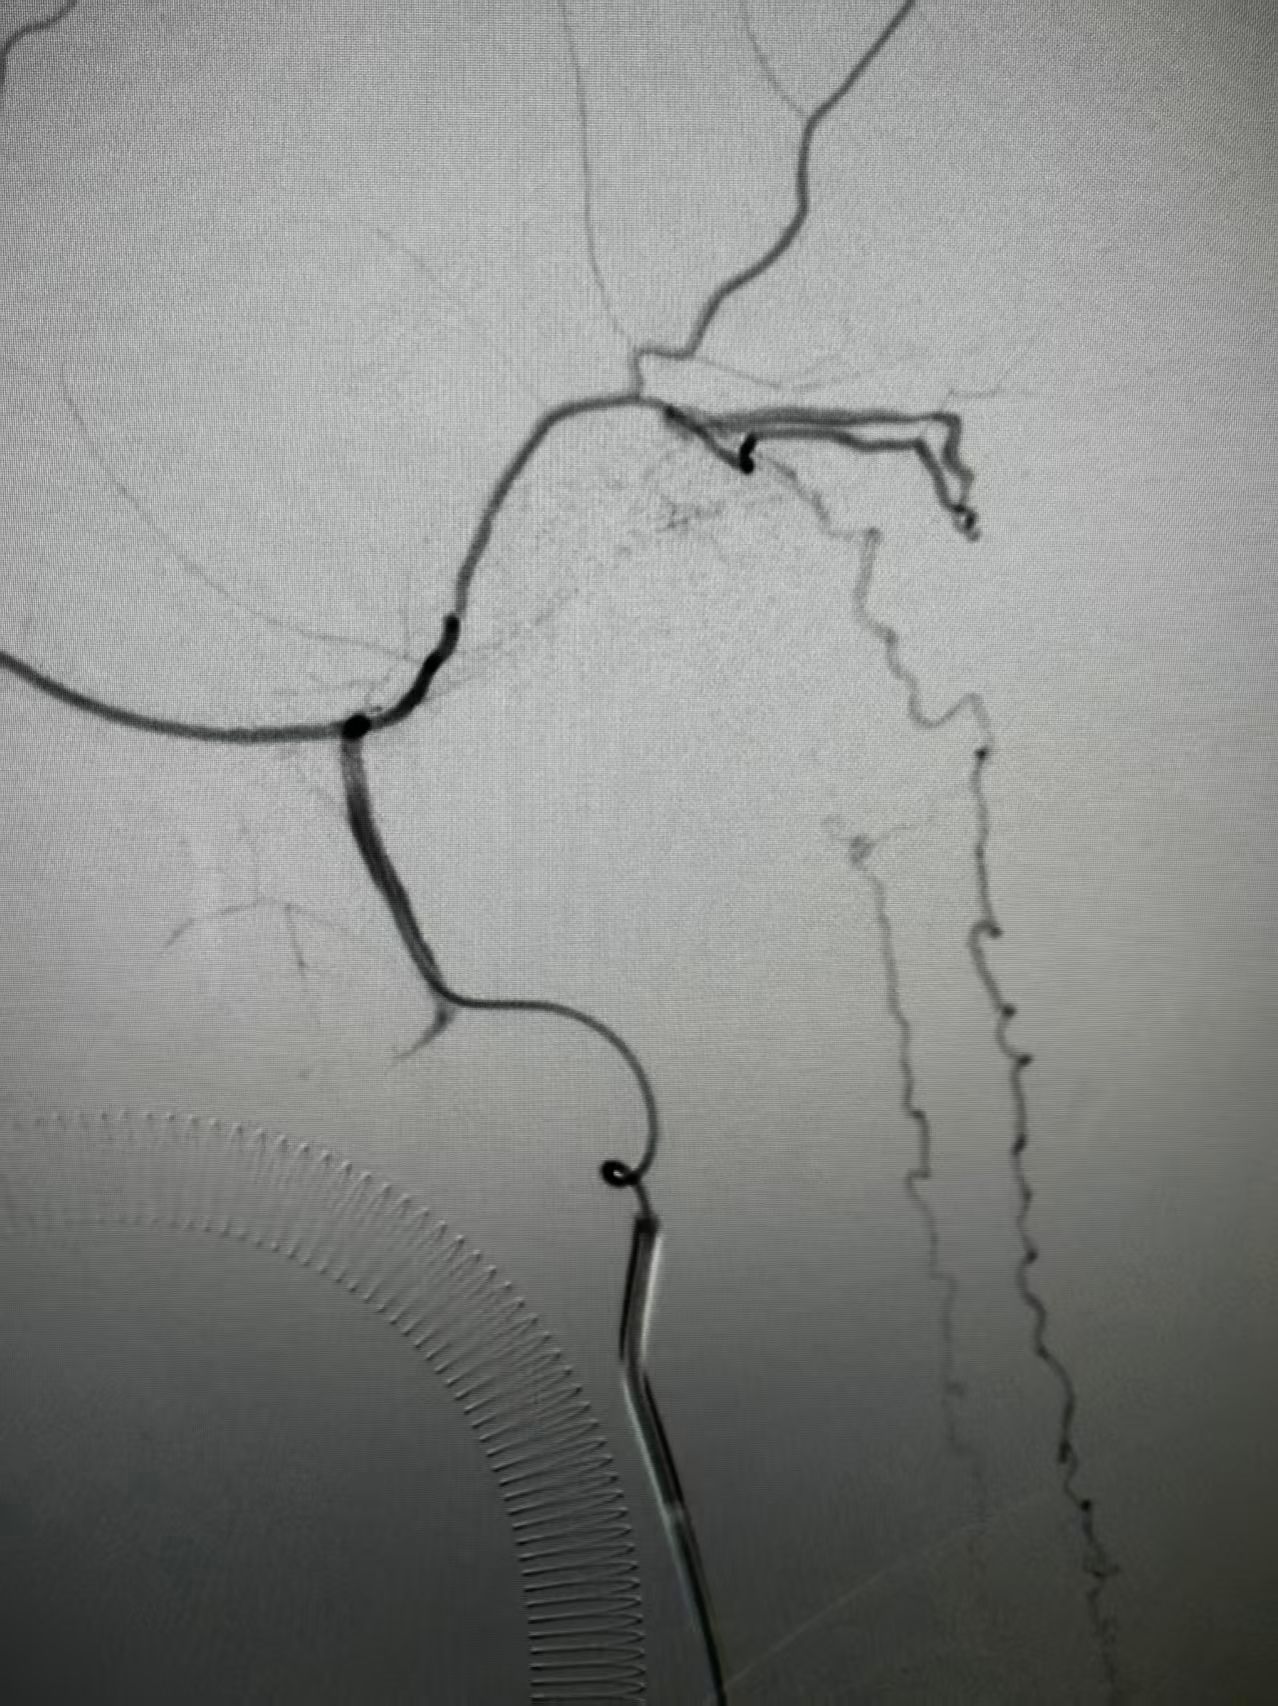

团队结合患者病史、影像学检查以及使用激素后加重的特征,讨论后认为动静脉瘘的可能性较大。但全脊髓造影并未发现硬脊膜动静脉瘘,那么,这个瘘会不会在颅内,只是朝脊髓引流了。根据这个猜测,许刚副主任医师团队为患者进行了全脑血管造影,初步的血管造影并未发现明显病灶。团队并未轻易放弃,又对可疑的各分支血管进行了超选择性造影。最终发现了该患者为脑膜中动脉及枕动脉脑膜支供血的一个非常细小的瘘口。该瘘位于岩骨脊,向下朝脊髓引流,不仔细研究很可能发现不了。

明确诊断后,许刚副主任医师、僧志远主治医师运用介入技术成功对该瘘口进行了栓塞,栓塞术后次日患者的双侧下肢感觉及运动功能就明显好转。一周后患者转当地医院继续康复治疗。

术前脑膜中超选侧位